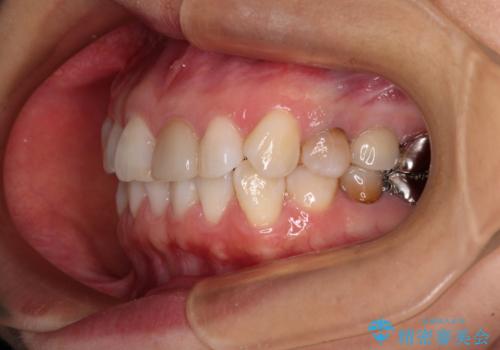

気になる下顎歯列のみをインビザラインで部分矯正

- 上下前歯のデコボコを気にして来院された患者様です。

カウンセリングにて詳しく話を聞いたところ、一番気になっているのは下顎前歯の叢生であり、上顎犬歯はあまり気になっていないとのことでした。

矯正治療は、歯の後戻りを抑制するために、治療終了後も保定装置をしっかりと使用していただくことが必須であるため、気になっている下顎だけを整えることで、その負担を半減できると考え、下顎のみの部分矯正として治療を行うこととしました。

装置としては、叢生の程度が強くなかったため、インビザラインの廉価版であるモデレート・パッケージを使用することとしました。

当院では治療前の歯列が整っていない限り、下顎前歯の舌側をワイヤーで固定するようにしています。下顎のみの部分矯正としたことで、マウスピース保定の負担を軽減することができました。

上顎は、失活して歯の色が変色しているため、将来的に補綴治療で自然な口元に仕上げていきたいとのことでした。